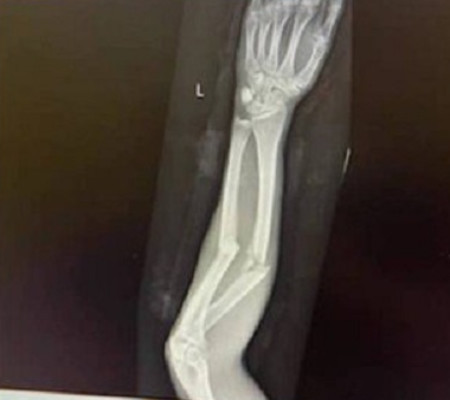

O jóquei Koby Jennings sofreu uma terrível fratura dupla no antebraço esquerdo ao cair de cavalo quando disputava um páreo em hipódromo de Goulburn (Austrália) na última sexta-feira (18/12). Apesar da cena assustadora, Jennings foi fotografado rindo quando era atendido por equipe de emergência. Com informações do Extra.

As imagens do jóquei no gramado e do exame de raio-x mostrando a fratura dupla viralizaram nas redes sociais.

Jennings foi operado no mesmo dia. Na cirurgia, ele recebeu duas placas de platina e parafusos para fixar os ossos do antebraço, contou o site "Racenet".Com mais de 300 vitórias na carreira e R$ 55 milhões em prêmios, o jóquei ficará por de atividade por cerca de três meses.